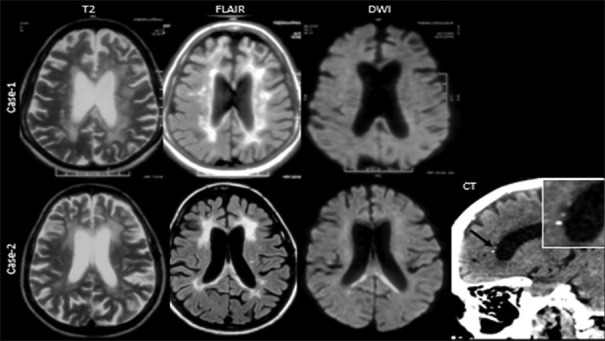

Abstract: CSF1R -related leukoencephalopathy is a rare, dominantly inherited leukoencephalopathy caused by mutations in the CSF1R gene that codes for colony-stimulating factor 1 receptor. We describe the clinical and neuroimaging features in three genetically confirmed cases (two women) of CSF1R -related leukoencephalopathy. The age at onset ranged from 41 to 45 years. Cognitive and behavioral disturbances were seen in all patients, and one patient had epilepsy. The movement disorders included parkinsonism, freezing of gait, cerebellar ataxia, tremors, etc., Pyramidal signs were noted in two patients. Magnetic resonance imaging of the brain showed signal changes in the white matter. Whole-exome sequencing revealed mutation in the CSF1R gene, confirming the diagnosis. A combination of rapidly progressive cognitive and behavioral disturbances with involvement of pyramidal, extrapyramidal, and characteristic neuroimaging suggests diagnosis. Currently, the treatment is symptomatic as there is no specific treatment for the disease and a multidisciplinary team is required for managing these patients. Hematopoietic stem cell transplantation has shown to benefit a few patients.